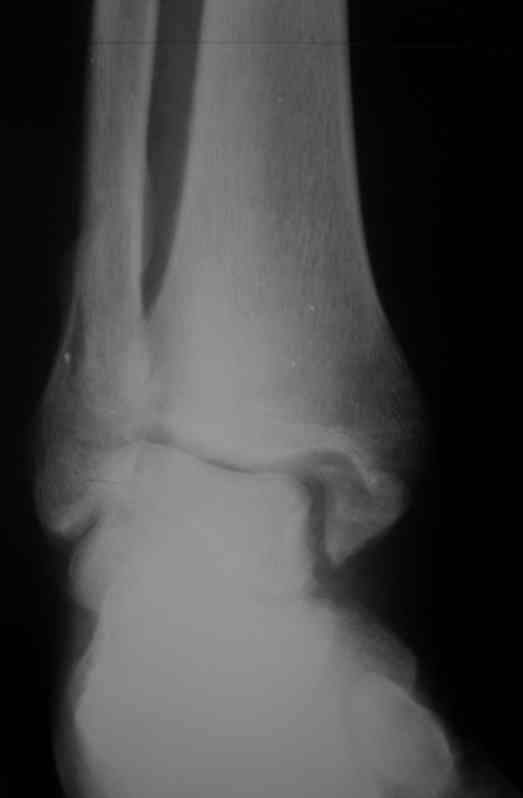

Уважаемые коллеги. Хотелось бы услышать ваше мнение по следующему случаю Обратился больной 23 года, травма 4 месяца назад - закрытый перелом наружной, внутренней лодыжки правой голени. Лечился консервативно, гипсовой иммобилизацией 8 недель, после снятия последней прошел курс восстановительного лечения. Беспокоят боли в области правого голеностопного сустава больше в проекции внутренней лодыжки, к вечеру. Отечность области сустава при физических нагрузках.Походка не изменена. Контуры правого голеностопного сустава сглажены. Имеется вальгусная установка правой пяточной кости. Объем движений в голеностопном суставе подошвенное / тыльное сгибание 50/0/80, безболезненные. Посоветуйте что делать в данной ситуации. Мне видится следующий вариант решения данной деформации: Восстановление нормальной анатомии голеностопного сустава - остеотомия малоберцовой кости и внутренней лодыжки, удалить все рубцы из области дистального межберцового синдесмоза, восстановить длину и устранить ротационное смещения наружной лодыжки.( встанет ли таранная кость на место?), фиксация наружной лодыжки пластиной, внутренней - винтами, дистального межберцового синдесмоза винтом. ЭОПом не располагаем. Что вы посоветуете? Где могут быть - технические трудности, <подводные камни>.

P.S. На боковой проекции таран выглядит несимпатично. Может быть изза качества снимка?

План вполне здравый. Но... Такое впечатление, что после устранения подвывиха суставные поверхности уже могут быть неконгруэнтны все равно.

То ли там есть импрессия в наружном отделе суставной площадки tibia, то ли не знаю что... IMHO не сильно криминальым выглядит и вариант

оставить как есть, пока не придет за артродезом.